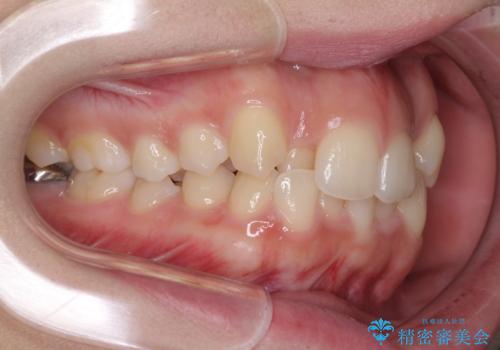

骨格的に左右にずれいている 前歯のデコボコをインビザラインで解消

- 前歯のデコボコと八重歯を気にして来院された患者様です。

叢生の程度は中等度であったため、IPR(歯と歯の間を削る)と歯列の側方拡大をメインに、インビザラインを用いて歯列を改善することとしました。

また、下顎骨の右側変位による右側臼歯の咬合を改善させるよう試みることとしました。

右側の咬合改善を目標に様々な手法を用いましたが、骨格的なズレによる不正咬合はインビザラインでは改善することができませんでした。